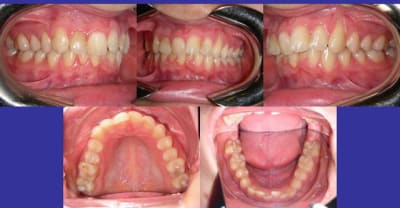

Attendre 6 mois et faire des Rx. de contrôle tous les 2 mois.

Si la situation se stabilise, j’utiliserai une mécanique à friction nulle, qui permettrai de remettre les dent dans le couloir physiologique de CHATEAU. Type Damon ou autre.

L’autre problème, et non des moindres, est celui de la responsabilisation possible si tu y touche.

Je demanderai donc, avant un avis universitaire.

C’est amusant, j’ai un cas identique après traitement.

La différence, c’est que c’est moi qui l’ai réalisé, ce traitement, avec avulsion de 14 et 24 !

Mais dans mon cas, les quatre rhizalyses étaient préexistantes et les déplacements ne les ont pas augmentées.

Je n’ai plus la panoramique de départ, juste la télé (c’est le confrère pédodontiste qui s’occupe de lui qui a tout le suivi radios), mais on voit quand même bien sur cette télé que les quatre incisives supérieures étaient plus courtes. On peut comparer avec la dernière télé. Pas de différence.

A méditer avant de crier haro sur un traitement orthodontique…

c'etait aussi ma premiere reaction mais que penses tu de l'option activateur plurifonctionnel(SB) qui respecterait les limites physiologiques des rhizalyses et donnerait de l'expansion(et alignement)

que penses tu de l'option activateur plurifonctionnel(SB) qui respecterait les limites physiologiques des rhizalyses et donnerait de l'expansion (et alignement)

---> Si quelqu'un me présente un cas similaire traité en 12-15 mois par SB avec un résultat équivalent au MB, je suis interessé.

est ce qu'ici la limite et le challenge sont le temps de traitement?

on a le choix entre ne rien faire pour ne pas risquer de rhizalyses et un activateur

qui fera expansion-alignement

le temps de traitement ne me semble pas un argument pour rejeter cette possibilite

En SB, pour aligner plus correctement ça peut ne pas prendre trop de temps, 6 à 18 mois, tout dependra de la réponse et de l'assiduité du patient. Bien evidemment que 6 à 18 mois ne suffiront pas à terminer le cas, en general il faut plutot compter 3 à 4 ans, mais en 2 à 6 mois on devrait déjà voir des choses bouger et se faire une idée sur la reponse.